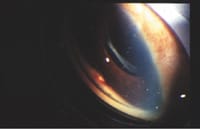

On post-op day 8, her vision was 20/80 and IOP was 36 mmHg. Slit lamp examination showed resolution of the hyphema and a flat, vascularized bleb. Gonioscopy revealed a blood clot in the sclerostomy site.

At this time, digital massage was performed without improvement in IOP or bleb elevation. Argon laser suture lysis was performed to cut one suture, and IOP dropped to 28 mmHg. The patient was started on dorzolamide 2% and timolol 0.5% (Cosopt) OD bid as a temporizing measure while tPA was obtained for intracameral injection.

On post-op day 9, visual acuity was 20/80 and IOP was 26 mmHg. The bleb was flat and there was still a clot within the sclerostomy site. TPA was administered intracamerally 10 mcg/0.1 cc for a total of 0.25 cc (25 mcg). Ten minutes after injection the IOP was 10 mmHg.